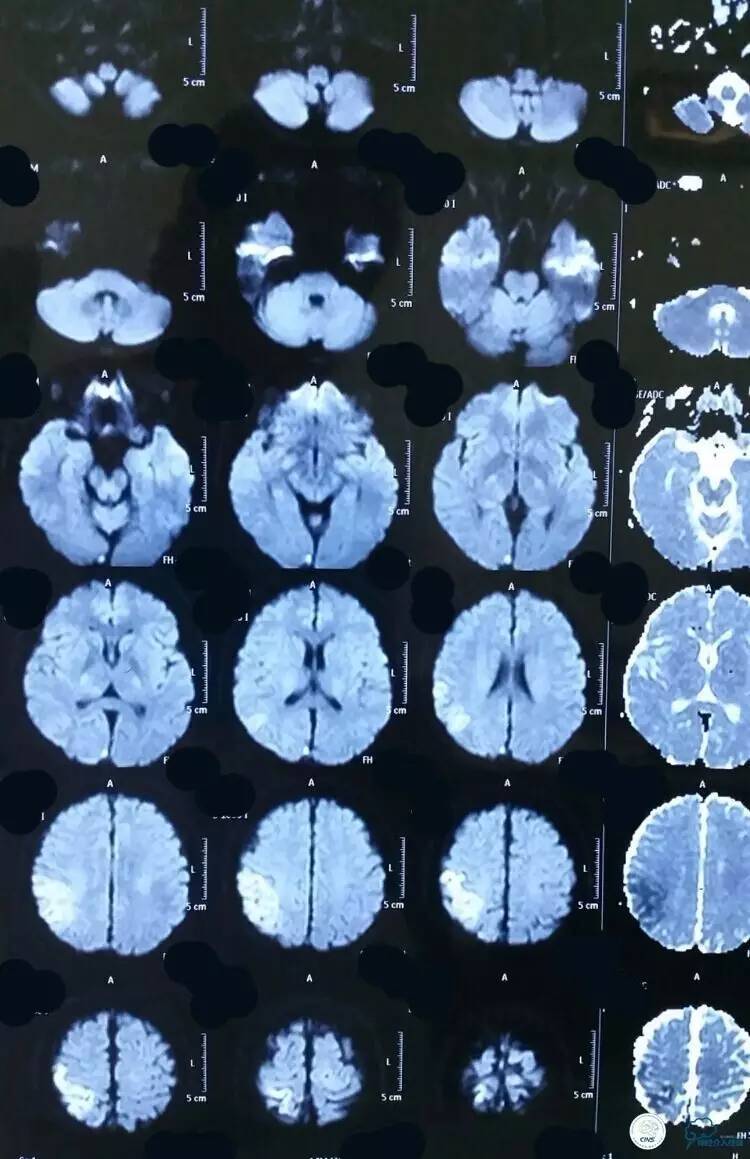

▼术前DWI:有静脉性脑梗塞

▼术前ADC: